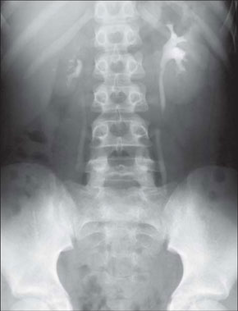

Рентгенограма хворих з СМР

При 1‑й степені закид контрасту з сечового міхура походить тільки в нерозширений сечовід.

При 2‑й степені заповнюють нерозширений сечовід і нерозширений чашечко-мискова система (ЧМС) нирок.

При 4‑й степені і вони стають заокругленими.

При 5‑й степені характеризується масивною делятацією і звивістю верхніх сечових шляхів.